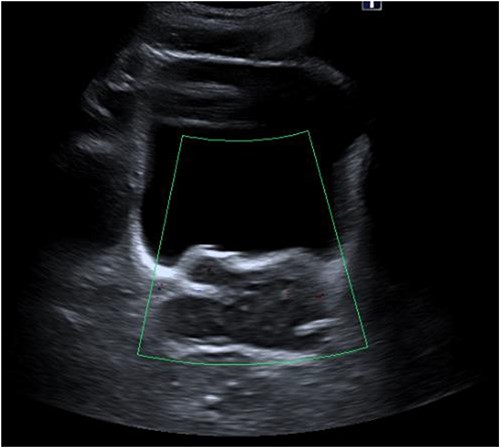

Laboratory tests of full blood count and liver function test were unremarkable with prostate specific antigen of 0.53. Mid-stream urine MCS did not show any infection and urine cytology was negative. Renal function test revealed progressive worsening of previously normal eGFR down to 27 ml/min. Initial renal tract ultrasound (Fig. 1) showed enlarged prostate indenting into the bladder base with high post micturition urine residual volume of 185 ml but no hydronephrosis. CT KUB (Fig. 2) showed irregularly enlarged prostate with bilateral hydroureteronephrosis. MRI prostate showed enlarged prostate with PIRADS 5 amorphous mass suspicious for carcinoma involving bilateral seminal vesicles and right vesicouretric bladder. FDG PET (Fig. 3) showed unusual distribution pattern of lymphoma involving the prostate with bilateral symmetrical renal, early pulmonary, and possibly right thyroid lobe involvement.

Renal ultrasound showing enlarged prostate indenting into the bladder.